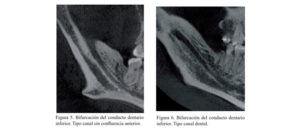

El objetivo del presente estudio fue evaluar los factores (referidos a la CBCT) que influyen en la toma de decisión en tratamientos para extracción de